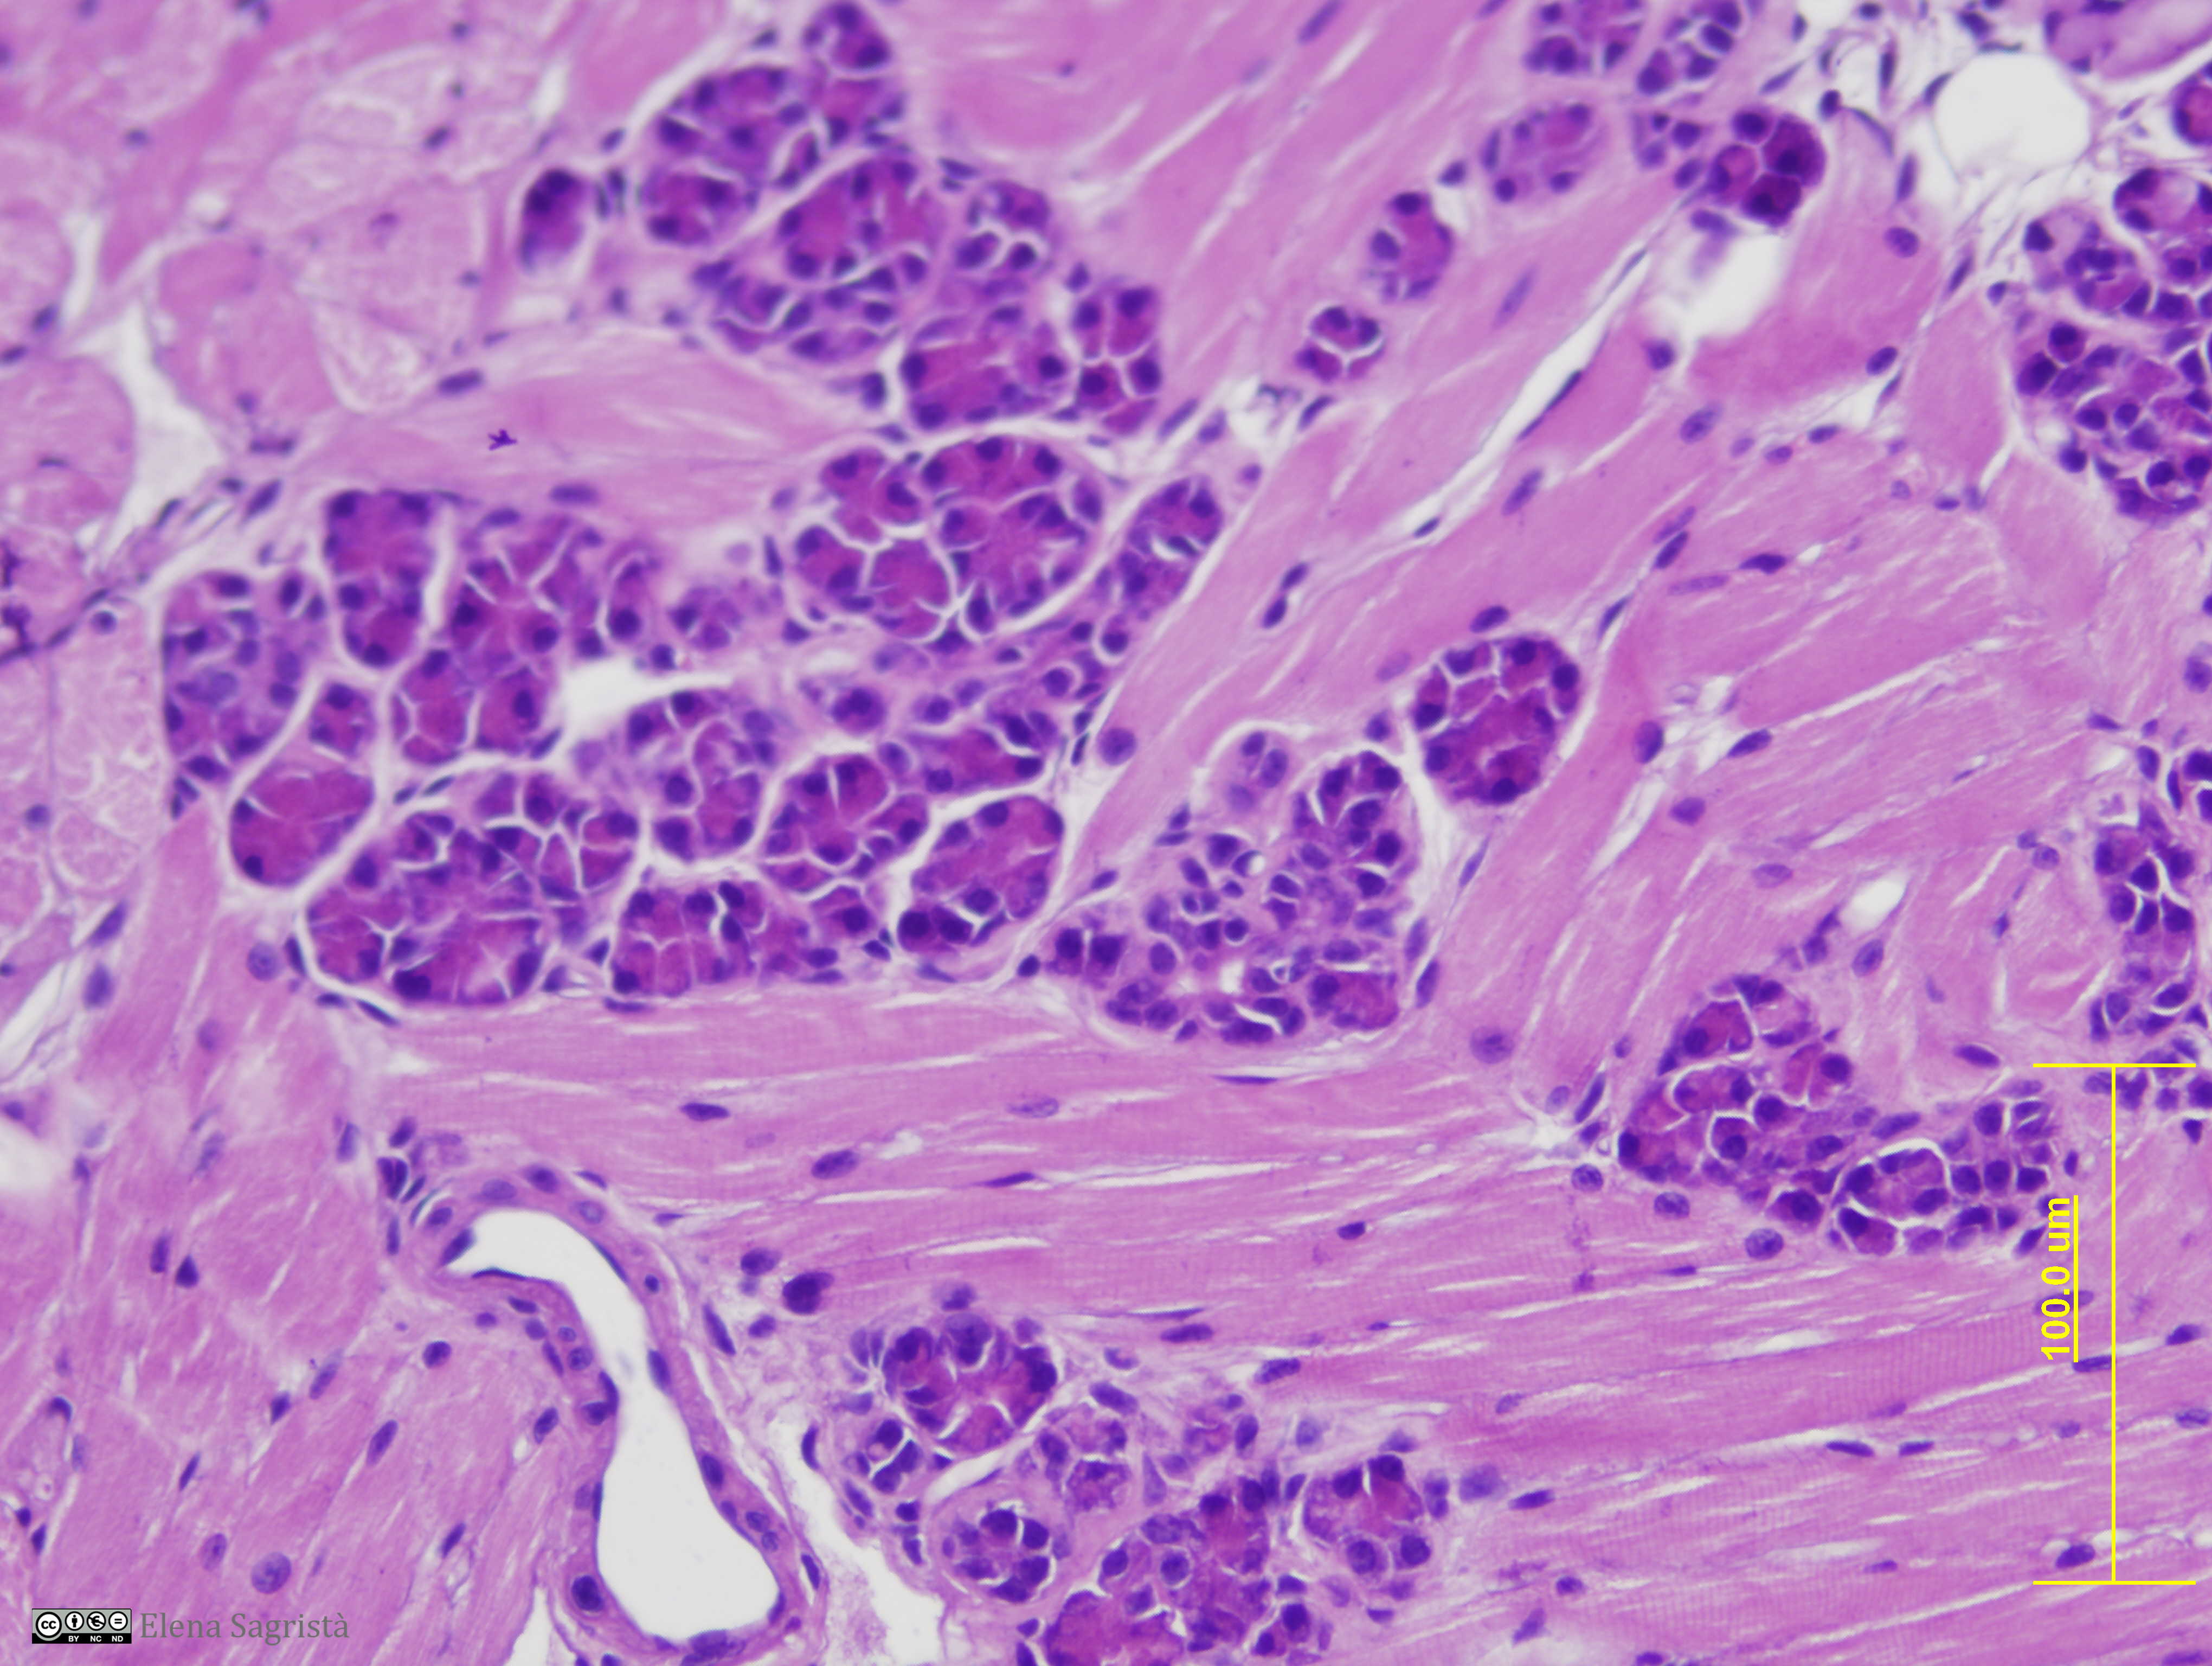

Histologia imatges: 01 Teixit epitelial

Imatges de preparacions histològiques de teixit epitelial. Microscopia òptica.